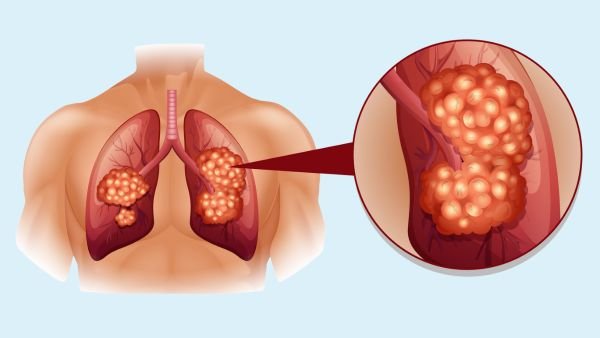

Air flows through your nose and mouth, deep into the lungs through large airways (bronchi) and small airways (bronchioles). These breathing tubes lead air into millions of tiny air sacs called alveoli. Within the walls of the air, sacs are a tissue called the interstitium. Much like a net, a collection of tiny blood vessels called capillaries surround each air sac.

The oxygen we breathe moves through the walls of the alveoli (including the interstitium) and into these surrounding capillaries, where the oxygen is picked up by red blood cells and carried to the heart. Carbon dioxide (CO2) moves in the opposite direction from O2 and is exhaled.

In IPF, the interstitium is thickened with scarring, making it difficult for oxygen to reach the capillaries. The scarring also makes the lungs “stiff” and difficult to inflate. Stiff lungs literally hold less air than normal lungs; that is, they have less filling capacity. This low lung capacity, along with the problem with oxygen passing through the walls of the air sacs, causes shortness of breath.

The amount of scarring can increase with time, making the lung even stiffer, further limiting its filling capacity, and limiting the ability of oxygen to pass through air sac walls. This scarring is generally not reversible.